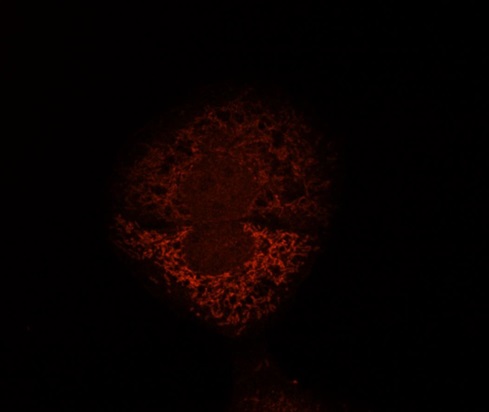

Human HepG2 cells fixed with 3.7% Formaldehyde in medium, blocking performed with 10% NGS in 1x PBS buffer + 0.1% Tween20. Incubated with Anti-Mitofilin/IMMT Polyclonal Antibody (bs-1824R) at a 1:10 dilution for 1hr at RT, followed by Anti-Rabbit secondary, Cy3 conjugate at a 1:300 dilution incubated at RT for 1hr. This image was kindly provided by an end-user.